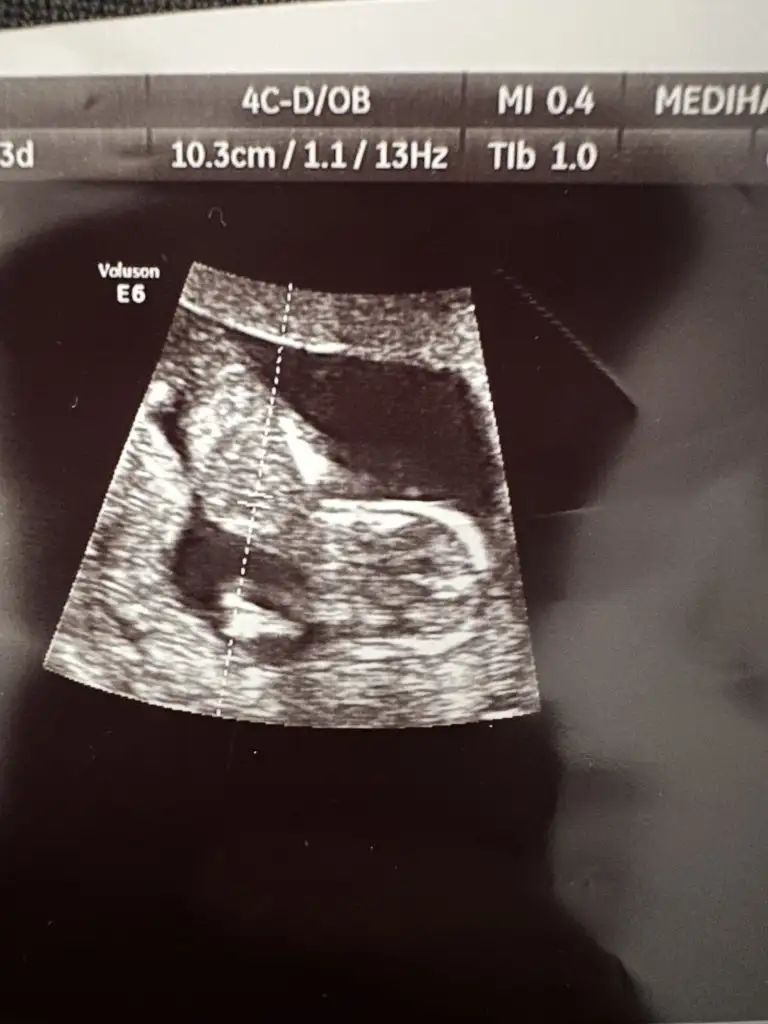

Bizi de yorumlayan biri olabilir mi şuan 12+3 ama fotoğrafta 11 haftalık doktor bir benzetmede bulundu ama net olmadığı için sevinemiyorum 😇

Eklentiler

• 20230216_125345.webp

20230216_125345.webp

29,9 KB · Görüntüleme: 82

Arkadaşlar bu teoriye göre yorum yapabilmek için cocugun sırt üstü şekilde durması gerekiyor ve bacakları da görüntüyü kapatmamalı, internetteki örneklerde genelde 90 derece duruyor bacaklar. Ayrıca 11 veya 12 haftalık olması gerekiyor. Bence konu sahibininki kız ama diğerlerini hiç anlayamadım